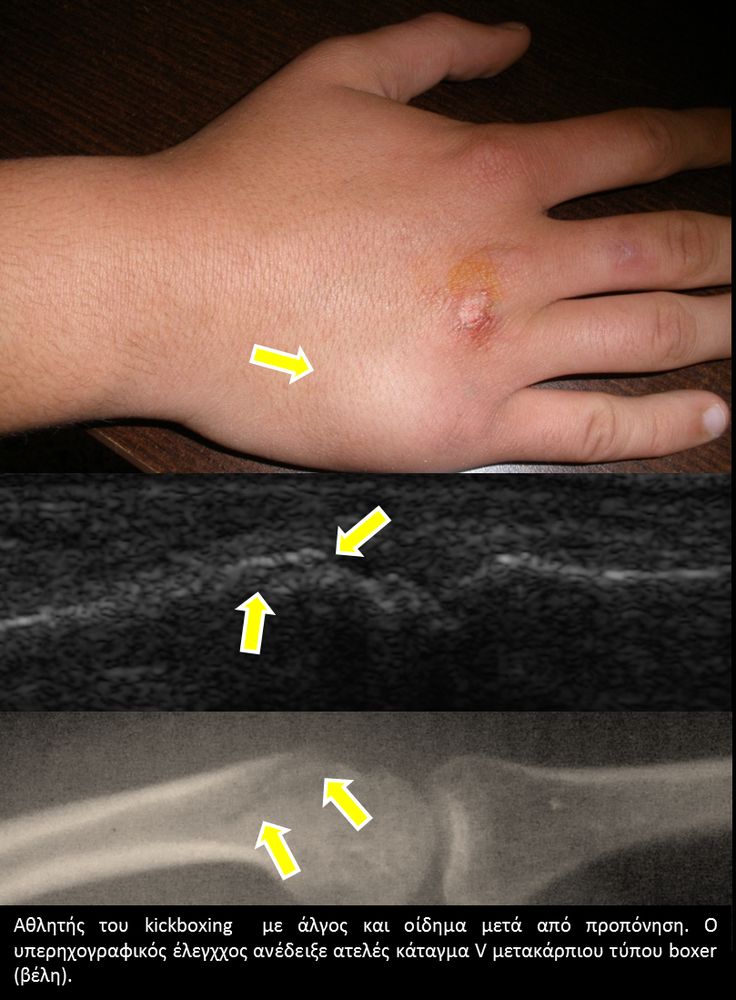

Είναι μια νέα μέθοδος που χρησιμοποιεί υψηλής ευκρίνειας υπερήχους για τη διάγνωση μυοσκελετικών παθήσεων που αφορούν τένοντες, μυς, συνδέσμους, νεύρα και περιφερικές αρθρώσεις. Η μέθοδος αναπτύχθηκε τα τελευταία χρόνια και αποτελεί αναπόσπαστο μέρος στη διαφορική διάγνωση παθήσεων που αφορούν τηνορθοπαιδική, αθλητιατρική, ρευματολογία και παιδιατρική.

Πρόκειται για υπερηχογράφημα υψηλής ευκρίνειας που επιτρέπει την λεπτομερέστατη απεικόνιση (σε επίπεδο χιλιοστού) ακόμη και πολύ μικρών/επιφανειακών ανατομικών δομών και απαιτεί ειδικό υπερηχογραφικό εξοπλισμό καθώς και εξειδίκευση του ακτινολόγου. Η εξέταση γίνεται με δυναμικό τρόπο, δηλ εκτελούνται δοκιμασίες κίνησης του μέλους που πάσχει, ώστε να αποκαλυφθεί η παθολογίαακόμη και όταν δεν είναι εμφανής σε θέση ηρεμίας. Επιπλέον, η εξέταση είναι ανώδυνη και ασφαλής και δεν περιλαμβάνει ακτινοβολία (CT), μαγνητικό πεδίο (MRI) ή παραμονή σε κλειστό χώρο και είναι πολύ ανεκτή τόσο σε ενήλικες όσο και σε παιδιά.

- Αθλητικές κακώσεις σε παιδιά (πχ αποφυσίτιδα)